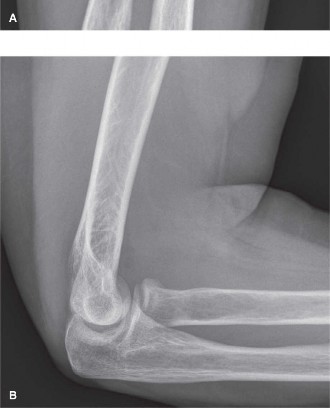

A 36-year-old, right-hand-dominant male presents to the emergency department with right arm and elbow pain after he fell over his handle bars while mountain biking. Physical examination finds the right upper extremity to be an isolated injury with the exception of some abrasions and ecchymosis about his face and bilateral upper extremities. Examining his elbow reveals tenderness about the radial head and marked pain with flexion, extension, pronation, and supination. There does not appear to be any mechanical block to motion although crepitation is appreciated with forearm rotation. Radiographs are shown in Figure 6–16A and B.

Figure 6–16 A–B

The correct response is “D.” The included images show a partial radial head fracture with displacement. While 2 mm of articular displacement is a relative indication for operative management, the only choice listed which is an agreed-upon surgical indication for partial radial head fractures is a fracture which produces a block to motion. Severe pain limiting a complete range of motion examination is not uncommon in the acute injury setting. Aspiration of elbow hematoma with or without injection of local anesthetic can assist with pain control and allow for a more accurate range of motion examination to determine whether or not the fracture is creating a mechanical block to motion. Other indications for operative treatment of a radial head fracture include comminuted fractures and those associated with complex injuries such as elbow dislocations, Monteggia fractures, or distal radioulnar joint (DRUJ) disruption. Figure 6–17 demonstrates the Mason classification of radial head fractures.